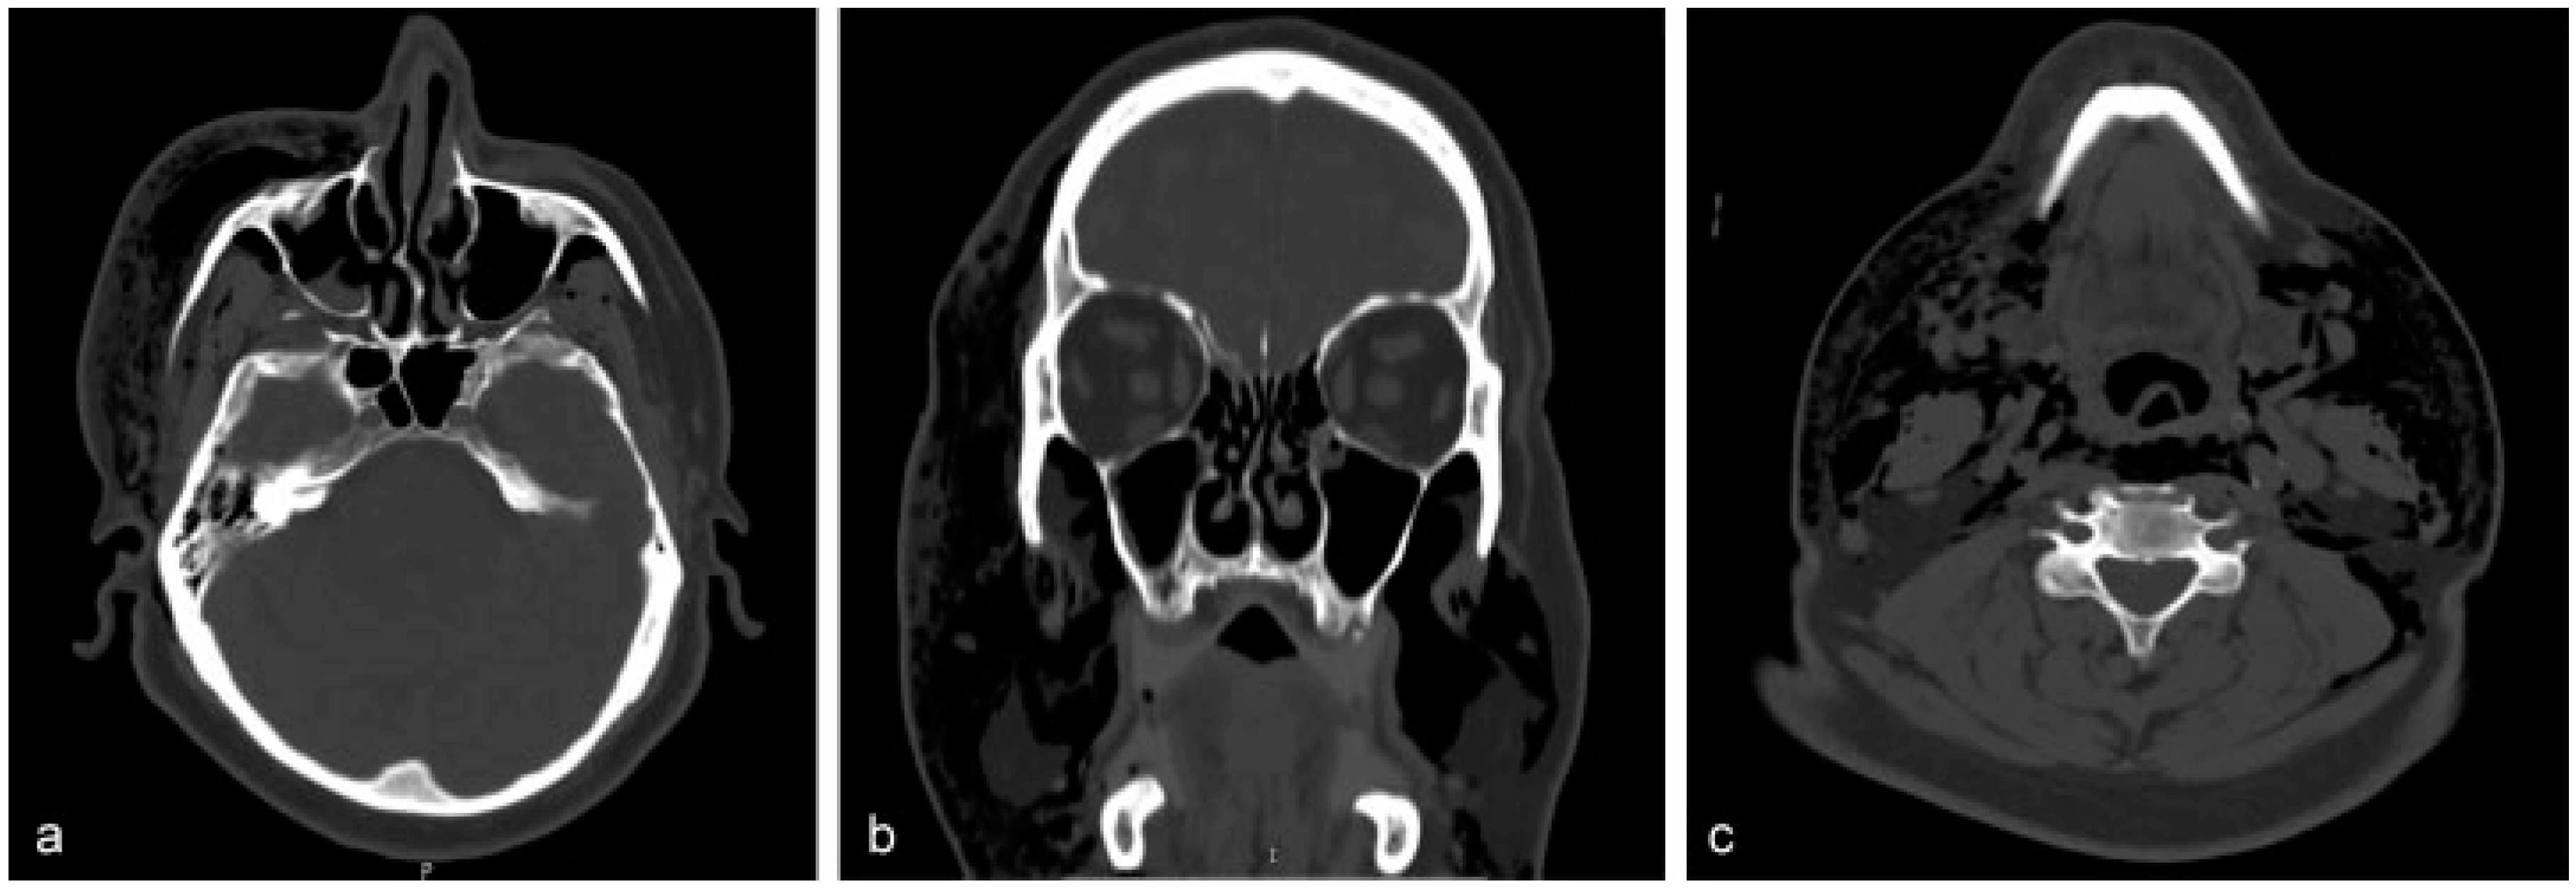

Routine blood tests, arterial blood gases, electrocardiography, and cardiac enzymes did not reveal any discrepancy. The anteroposterior and lateral views of plain radiographs of the neck showed scattered and lucent streaks owing to the presence of free air (Figure 1). Full-body computed tomo-graphic (CT) scan documented a nondisplaced fracture of right anterior sinus wall extending to the base of frontal process of ipsilateral maxillary bone (Figure 2a). Besides, it demonstrated pneumo-orbitus and massive emphysema that either occupied or extended to the following spaces: right temporal, bilateral buccal, bilateral parapharyngeal, bilateral carotid, retropharyngeal, prevertebral, visceral, anterior neck, and right posterior cervical (Figure 2b,c). The air had also spread to subcutaneous tissue of the left anterior chest wall and to the superior mediastinum, both retrosternally and between left common carotid and subclavian artery (Figure 3 and Figure 4). Neither thoracic CT nor chest plain radiographs evidenced signs of rib or clavicle fracture.

Figure 2.

(a) The source of air leakage: the anterior maxillary wall. (b,c) The extensions of the air to various sites and spaces of cervicofacial region.